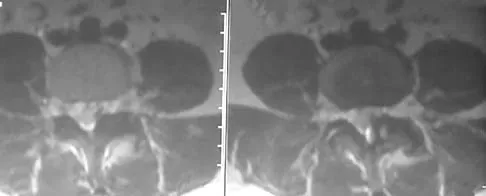

A 13-year-old girl injures her ankle playing soccer. Radiographs reveal a displaced Tillaux fracture. CT scans are shown in Figure 25. What is the most important consideration for appropriate management?